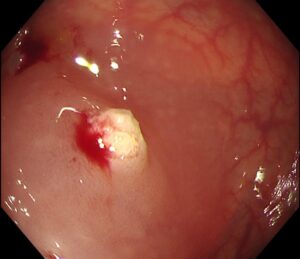

👉 スネアを締め、高周波電流で焼き切ります(写真6)

(写真6)

💫 術中の出血もなく、安全に切除完了(写真7)!

(写真7)

術後経過も良好で、出血などの合併症も一切ありませんでした🙆♀️